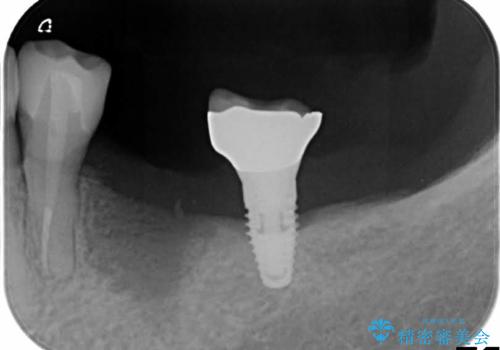

- 単独のインプラント補綴にて咬合の回復を計画した。

インプラント治療は、骨が十分になくてもさまざまな補助処置を行うことで可能になります。

インプラントの種類:straumann SLActive

かぶせ物の種類:Bellezza screw retain